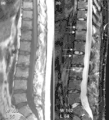

(a) T1-weighted and (b) short tau inversion recovery (STIR) magnetic resonance images of منطقة قطنية and lower صدر الإنسان spine in psoriatic arthritis. Signs of active inflammation are seen at several levels (arrows). In particular, قائمة مصطلحات تشريح المواضع (طب) spondylitis is seen at level L1/L2 and an inflammatory Andersson lesion at the upper vertebral endplate of L3.